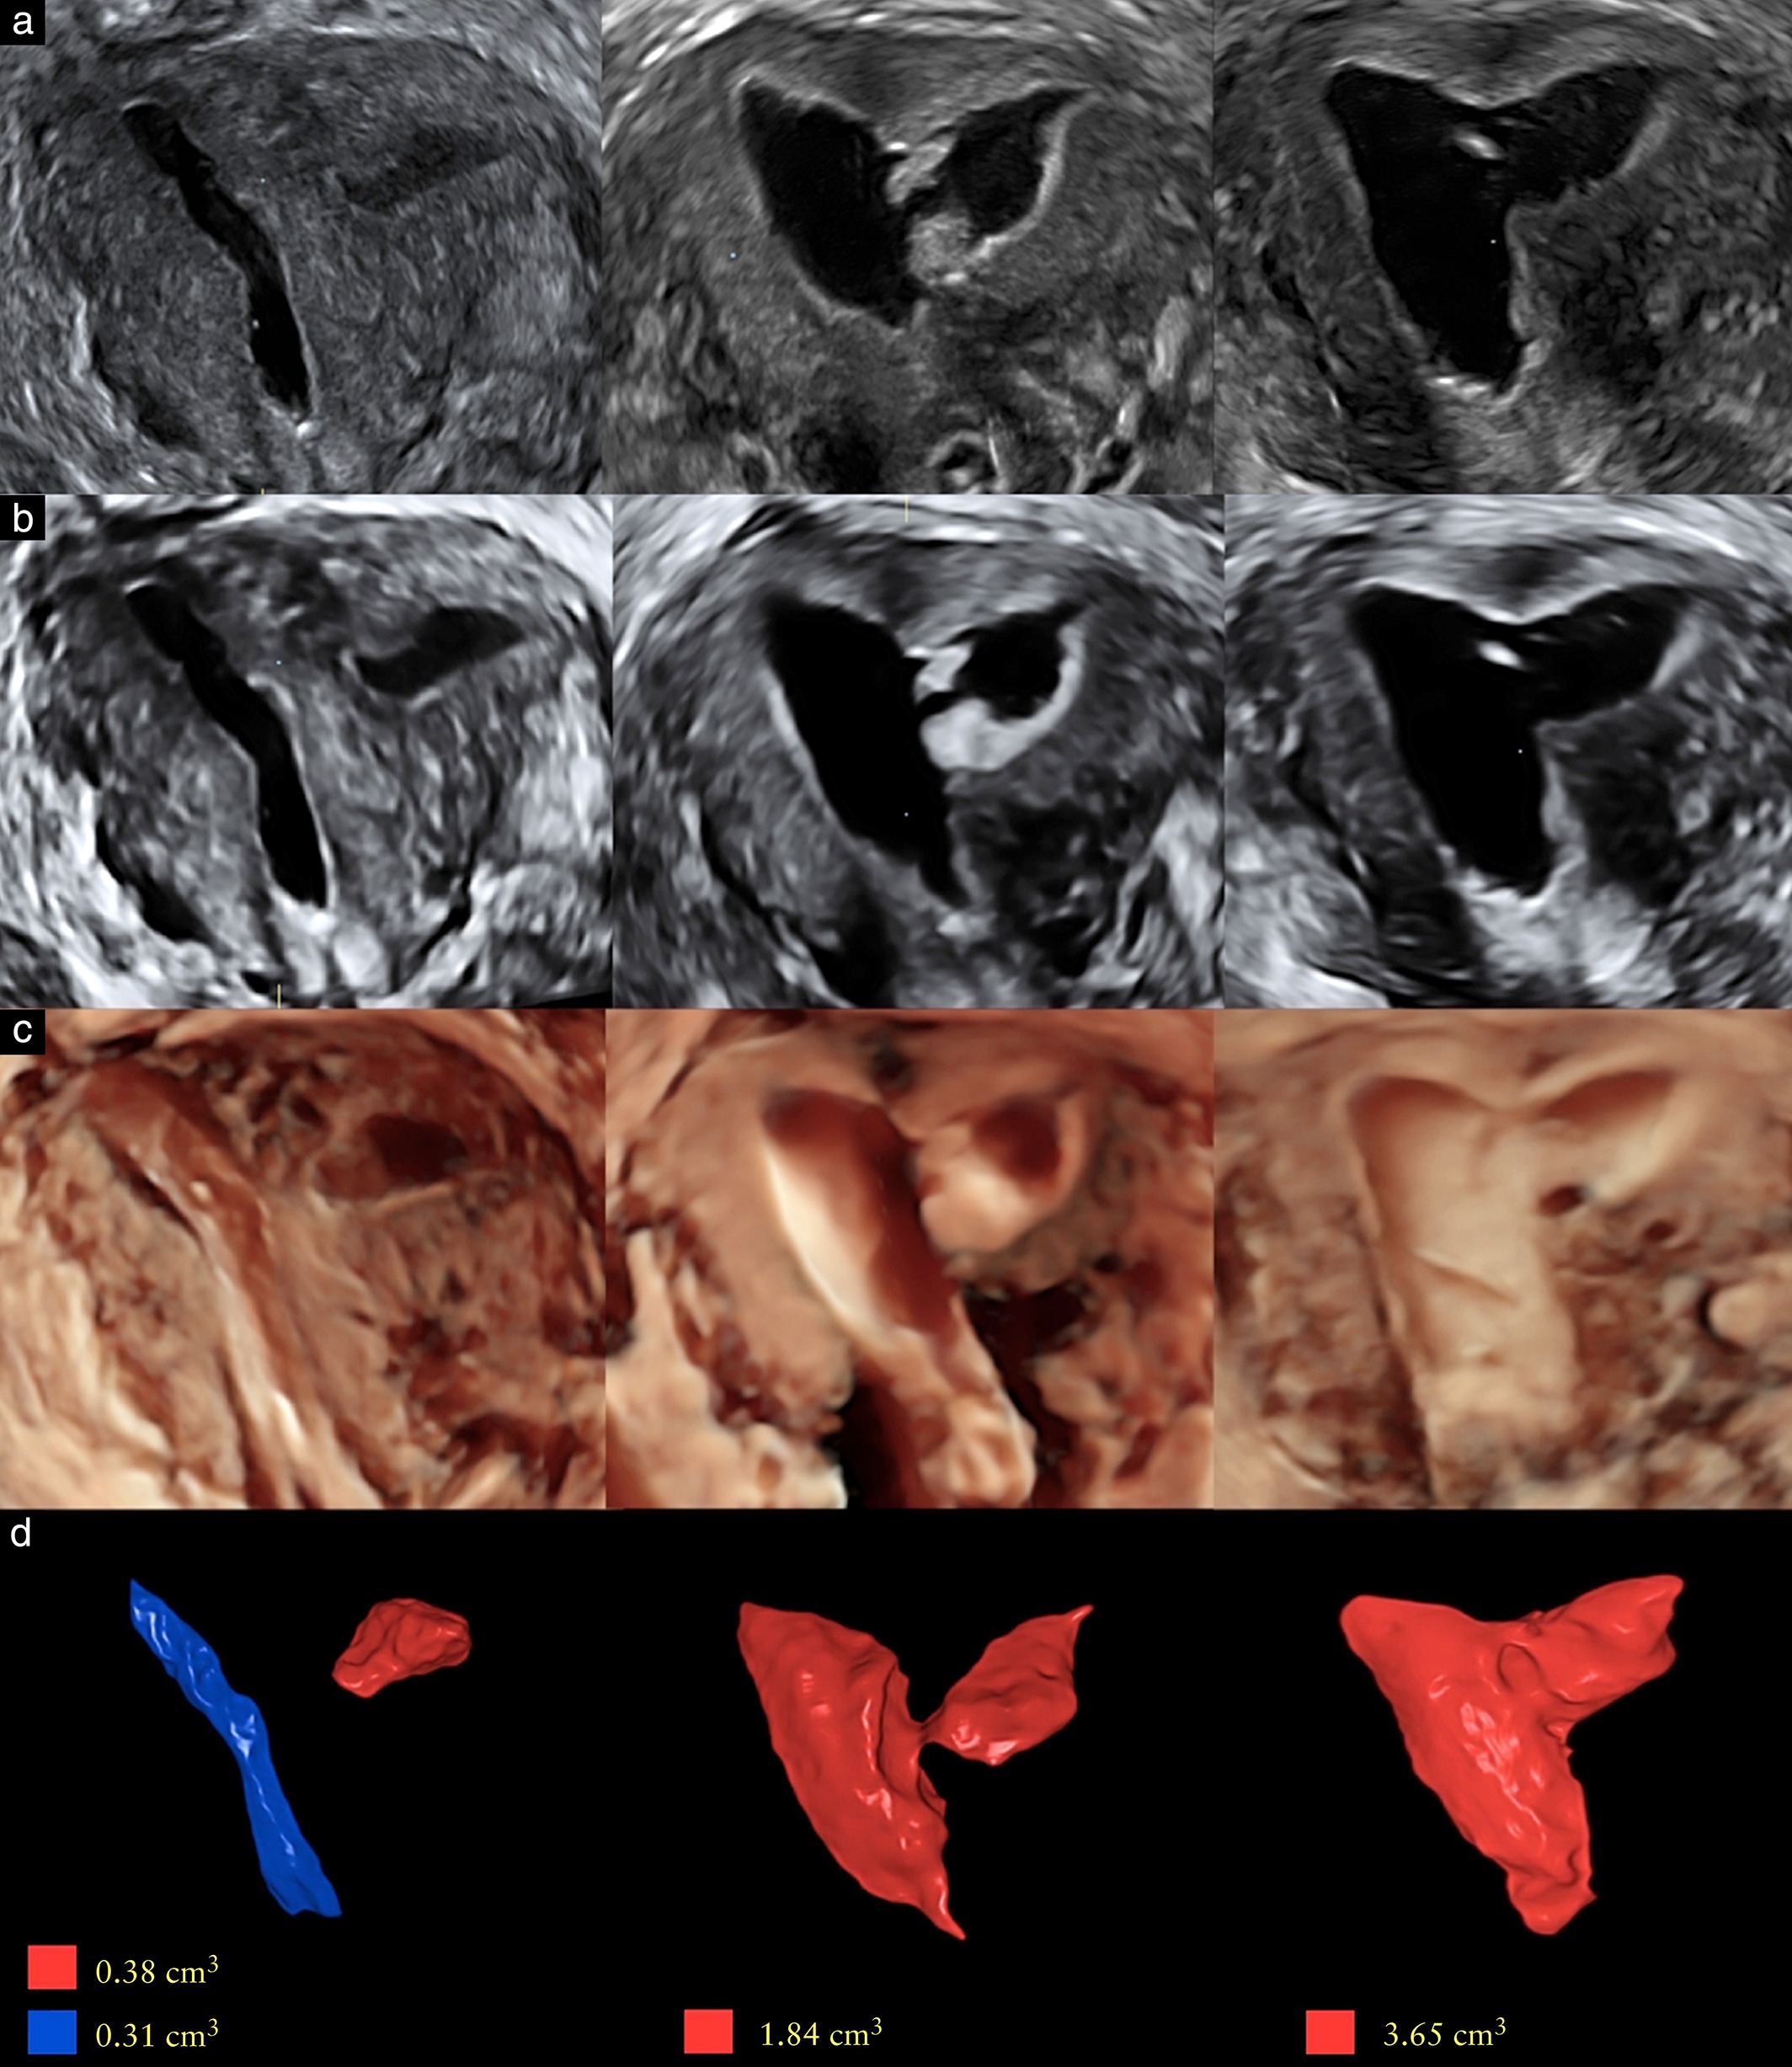

Evaluation of uterine niche by three‐dimensional sonohysterography and volumetric quantification: techniques and scoring classification system

Diagnostic accuracy of three-dimensional sonohysterography compared with office hysteroscopy and its interrater/intrarater agreement in uterine cavity assessment after hysteroscopic metroplasty

Role of morphologic characteristics of the uterine septum in the prediction and prevention of abnormal healing outcomes after hysteroscopic metroplasty